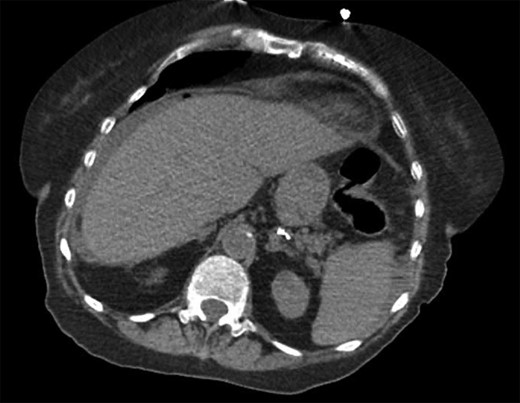

She was a former smoker with past medical history of hypertension, cerebrovascular event, hypothyroidism, and hyperlipidemia, and esophagogastroduodenoscopy and colonoscopy for gastrointestinal bleed, without past surgical history. On physical exam, she was normothermic, tachycardic, hypotensive and saturating 100% on room air. She had a distended, diffusely tender abdomen with guarding and rebound tenderness. Laboratory results were notable for leukocytosis with a left shift, chronic anemia, and acute kidney injury. Computed tomography of the chest, abdomen, and pelvis showed esophageal thickening, free air under the diaphragm, duodenal inflammation, generalized mesenteric fat stranding, free fluid in the abdomen and pelvis, and a thickened and inflamed bladder wall with irregular foci of hyperintensity within the bladder lumen and a left hydroureteronephrosis (Figs 1–3).

Transverse computed tomography showing intra-peritoneal free air under the diaphragm.